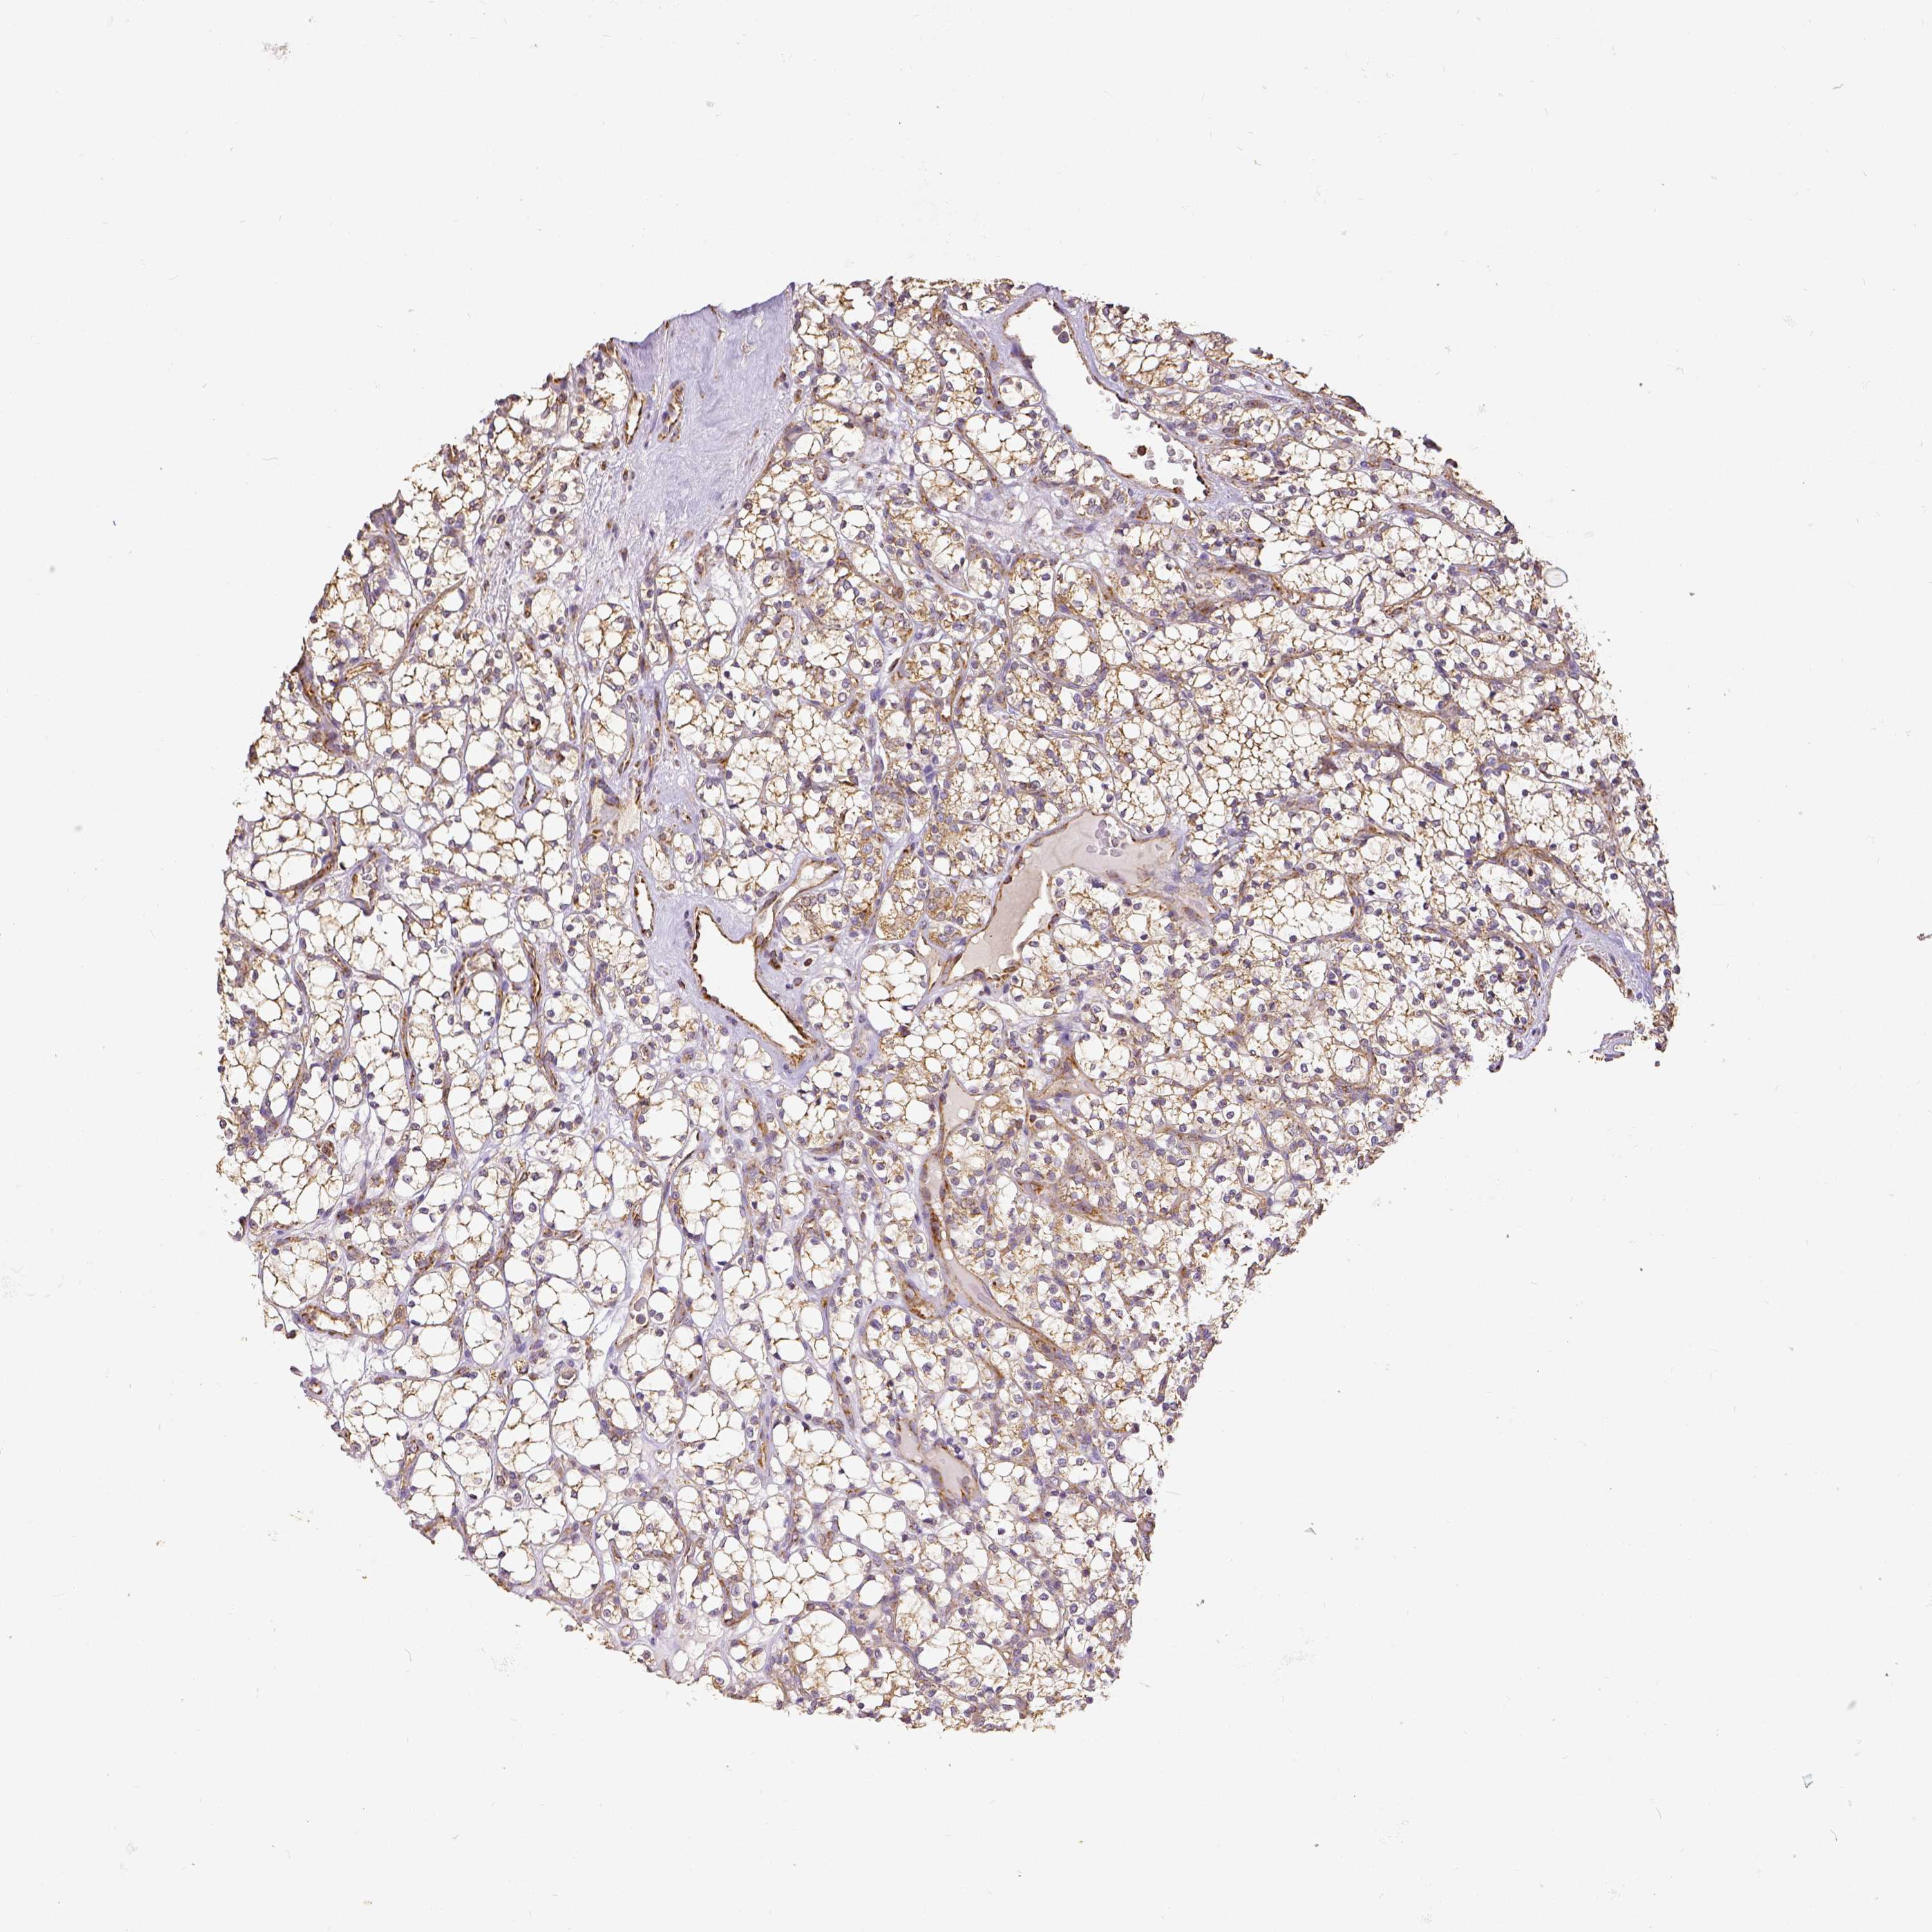

KIDNEY RENAL CLEAR CELL CARCINOMA (VALIDATION) - Interactive survival scatter ploti

The Survival Scatter plot shows the clinical status (i.e. dead or alive) for all individuals in the patient cohort, based on the same data that underlies the corresponding Kaplan-Meier plots. Patients that are alive at last time for follow-up are shown in blue and patients who have died during the study are shown in red.

The x-axis shows the expression levels (FPKM) of the investigated gene in the tumor tissue at the time of diagnosis. The y-axis shows the follow-up time after diagnosis (years). Both axes are complimented with kernel density curves demonstrating the data density over the axes. The top density plot shows the expression levels (FPKM) distribution among dead (red) and alive patients (blue). The right density plot shows the data density of the survived years of dead patients with high and low expression levels respectively, stratified using the cutoff indicated by the vertical dashed line through the Survival Scatter plot. This cutoff is automatically defined based on the FPKM cutoff that minimizes the p-score. The cutoff can be changed by dragging the vertical line or by entering a cutoff value in the square labeled "Current cut-off".

Under the Survival Scatter plot the p-score landscape (black curve; left axis) is shown together with dead median separation (red curve; right axis). Dead median separation is the difference in median mRNA expression between patients who have died with high and low expression, respectively. It is calculated as follows: median FPKM expression of dead patients with high expression - median FPKM expression of dead patients with low expression. This is intended to aid the user in visually exploring custom cutoffs and the associated p-scores and dead median separation.

Individual patient data is displayed and can be filtered by clicking on one or more of the category buttons on the top of the page. Categories describing expression level and patient information include: high, low, alive, dead, female, male and tumor stages. The scale of the x-axis can be toggled between linear and log-scale by clicking on the "x log" button. Mouse-over function shows TCGA ID, patient information and mRNA expression (FPKM) for each patient.

& Survival analysisi

Kaplan-Meier plots summarize results from analysis of correlation between mRNA expression level and patient survival. Patients were divided based on level of expression into one of the two groups "low" (under cut off) or "high" (over cut off). X-axis shows time for survival (years) and y-axis shows the probability of survival, where 1.0 corresponds to 100 percent.

SDHB is not prognostic in Kidney Renal Clear Cell Carcinoma (validation)

Best expression cut offi

Based on the FPKM value of each gene, patients were classified into two groups and association between prognosis (survival) and gene expression (FPKM) was examined. The best expression cut-off refers the FPKM value that yields maximal difference with regard to survival between the two groups at the lowest log-rank P-value. Best expression cut-off was selected based on survival analysis .

When clicking on this number, the vertical dashed line indicating cut-off, the interactive survival plot, and the Kaplan-Meier curve will be adjusted to show results based on the best expression cut-off.

: 107.81

P scorei

Log-rank P value for Kaplan-Meier plot showing results from analysis of correlation between mRNA expression level and patient survival.

N/A

TCGA RNA samplesi

RNA-seq data is reported as average FPKM (number Fragments Per Kilobase of exon per Million reads), generated by the The Cancer Genome Atlas (TCGA) .

Normal distribution across the dataset is visualized with box plots, shown as median and 25th and 75th percentiles. Points are displayed as outliers if they are above or below 1.5 times the interquartile range. FPKM values of the individual samples are presented next to the box plot.

Average pTPM 115.2

Number of samples 100